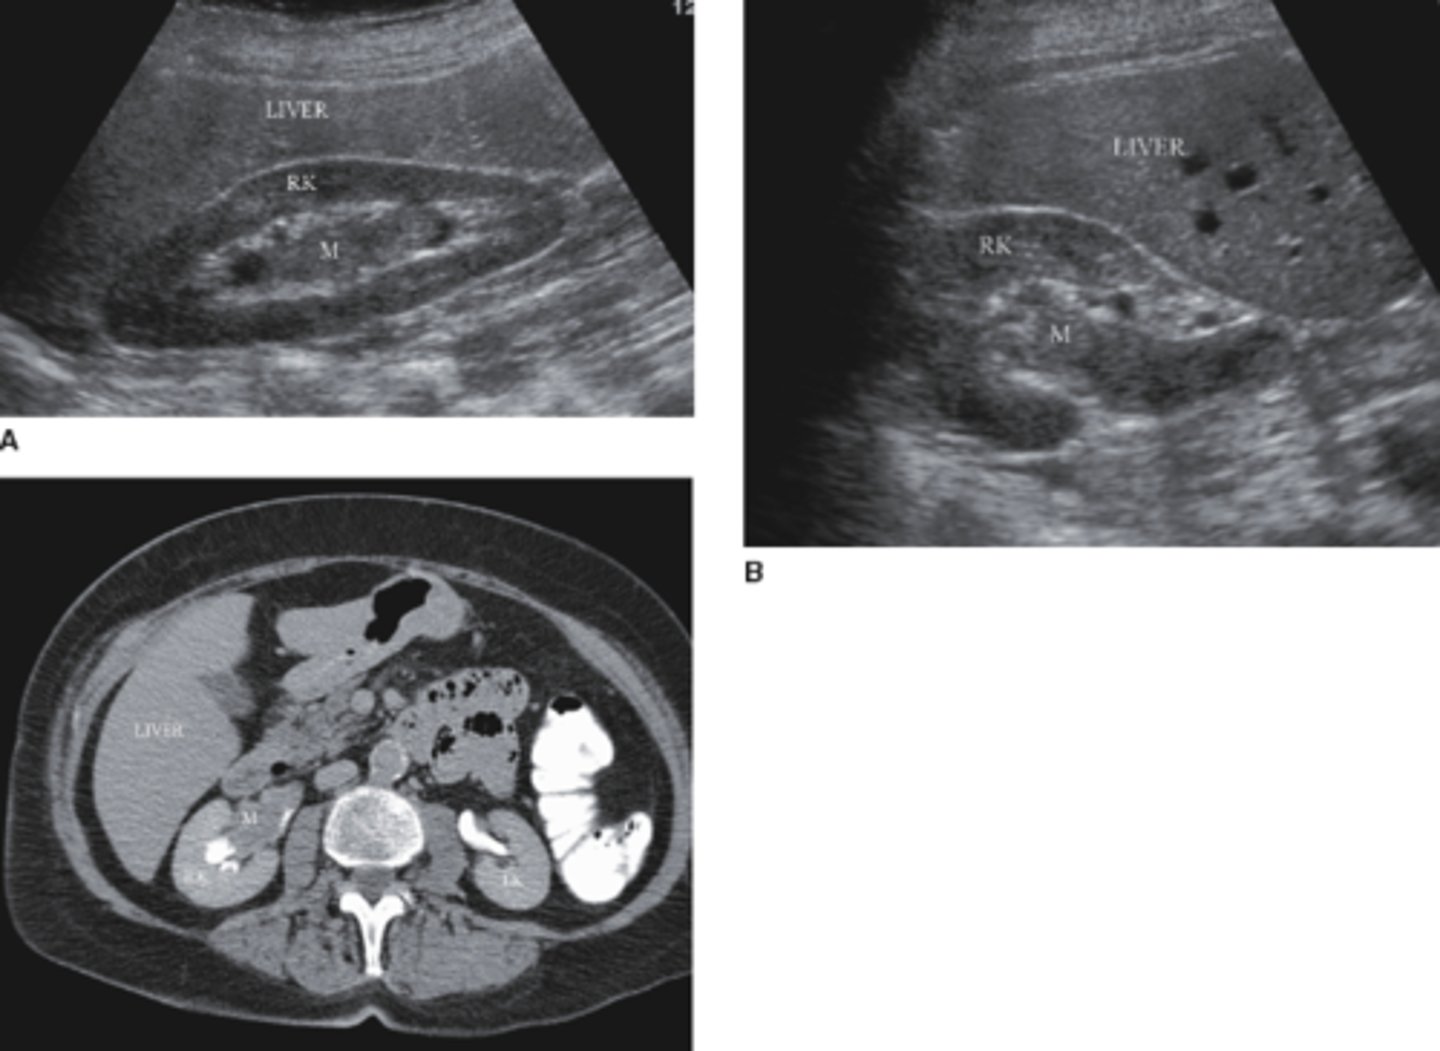

7. The 64-year-old patient in Figure 7-43 was suffering from anorexia, gross hematuria, flank pain, and had a history of smoking. Which of the following would be the most likely diagnosis for the mass (M) noted in this image?

a. Hypernephroma

b. Angiomyolipoma

c. TCC

d. Renal hematoma

a. Hypernephroma (RCC)

19. Figure 7-45 is an image of a 61-year-old male with gross hematuria. Which of the following would be the most likely diagnosis for the mass (M) noted in this transverse image?

a. Renal adenoma

b. TCC

c. Renal hamartoma

d. Renal hyponephroma